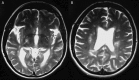

A 54-year-old woman presented to the ophthalmology emergency department with a 10-day history of blurred vision. The best-corrected visual acuities and Ishihara colour vision were bilaterally reduced with a left relative afferent pupillary defect. Slit-lamp examination was otherwise normal. Retrobulbar optic neuritis (ON) was presumed as she had suffered with this previously and was known to have multiple sclerosis (MS). She was recalled the following week for visual field (VF) testing, which was not available at the time of presentation. VFs demonstrated an incongruous left homonymous hemianopia. She was immediately referred to the medical team to investigate for a stroke, which was subsequently excluded. Thereafter, a trial of pulsed methylprednisolone was commenced, resulting in near complete resolution of the hemianopia. This case demonstrates not only the importance of VF testing, but also how ON may present with any field defect, including mimicking a stroke, a point valuable to ophthalmologists and medics alike.